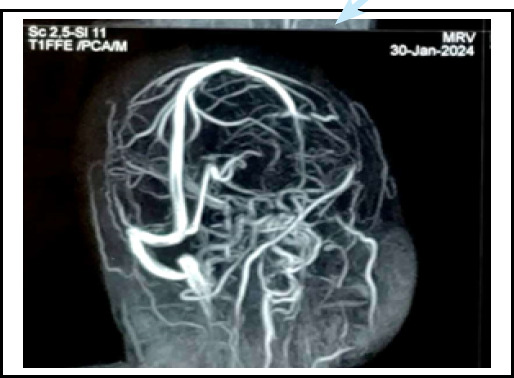

Pregnancy is the pro-thrombotic state. The objective of this report is to highlight the rare occurance of postpartum cavernous sinus thrombosis associated with eclampsia and gestational diabetes mellitus, emphasizing its clinical presentation. A 25-year-old Muslim female came with the complaint of headache,post auricular and right parietal region on 8th day post-partum. She had a history of postpartum eclampsia and Gestational Diabetes Mellitus for which she was treated with magnesium sulfate and oral hypoglycaemic agents respectively. MRV showed a filling defect in right transverse sinus, sigmoid sinus, and internal jugular vein. She was then admitted to the ward and was treated with heparin and antibiotics. She was then discharged on oral rivaroxaban. As pregnancy is itself a state of hyper-coagulable state, there seems to be a significant thrombosis risk. Hence clinicians should be aware of the possible thrombotic disorder in the background of this vignette.

妊娠是促血栓形成的状态。本报告的目的是强调产后海绵窦血栓形成合并子痫和妊娠糖尿病的罕见发生,并强调其临床表现。25岁穆斯林女性,产后第8天主诉头痛、耳后及右顶骨区。患者有产后子痫和妊娠期糖尿病病史,曾分别给予硫酸镁和口服降糖药治疗。MRV显示右横窦、乙状窦及颈内静脉充盈缺损。随后,她住进了病房,接受了肝素和抗生素治疗。她随后口服利伐沙班出院。由于妊娠本身就是一种高凝状态,因此似乎存在明显的血栓形成风险。因此,临床医生应该意识到在这个小插曲的背景下可能的血栓性疾病。